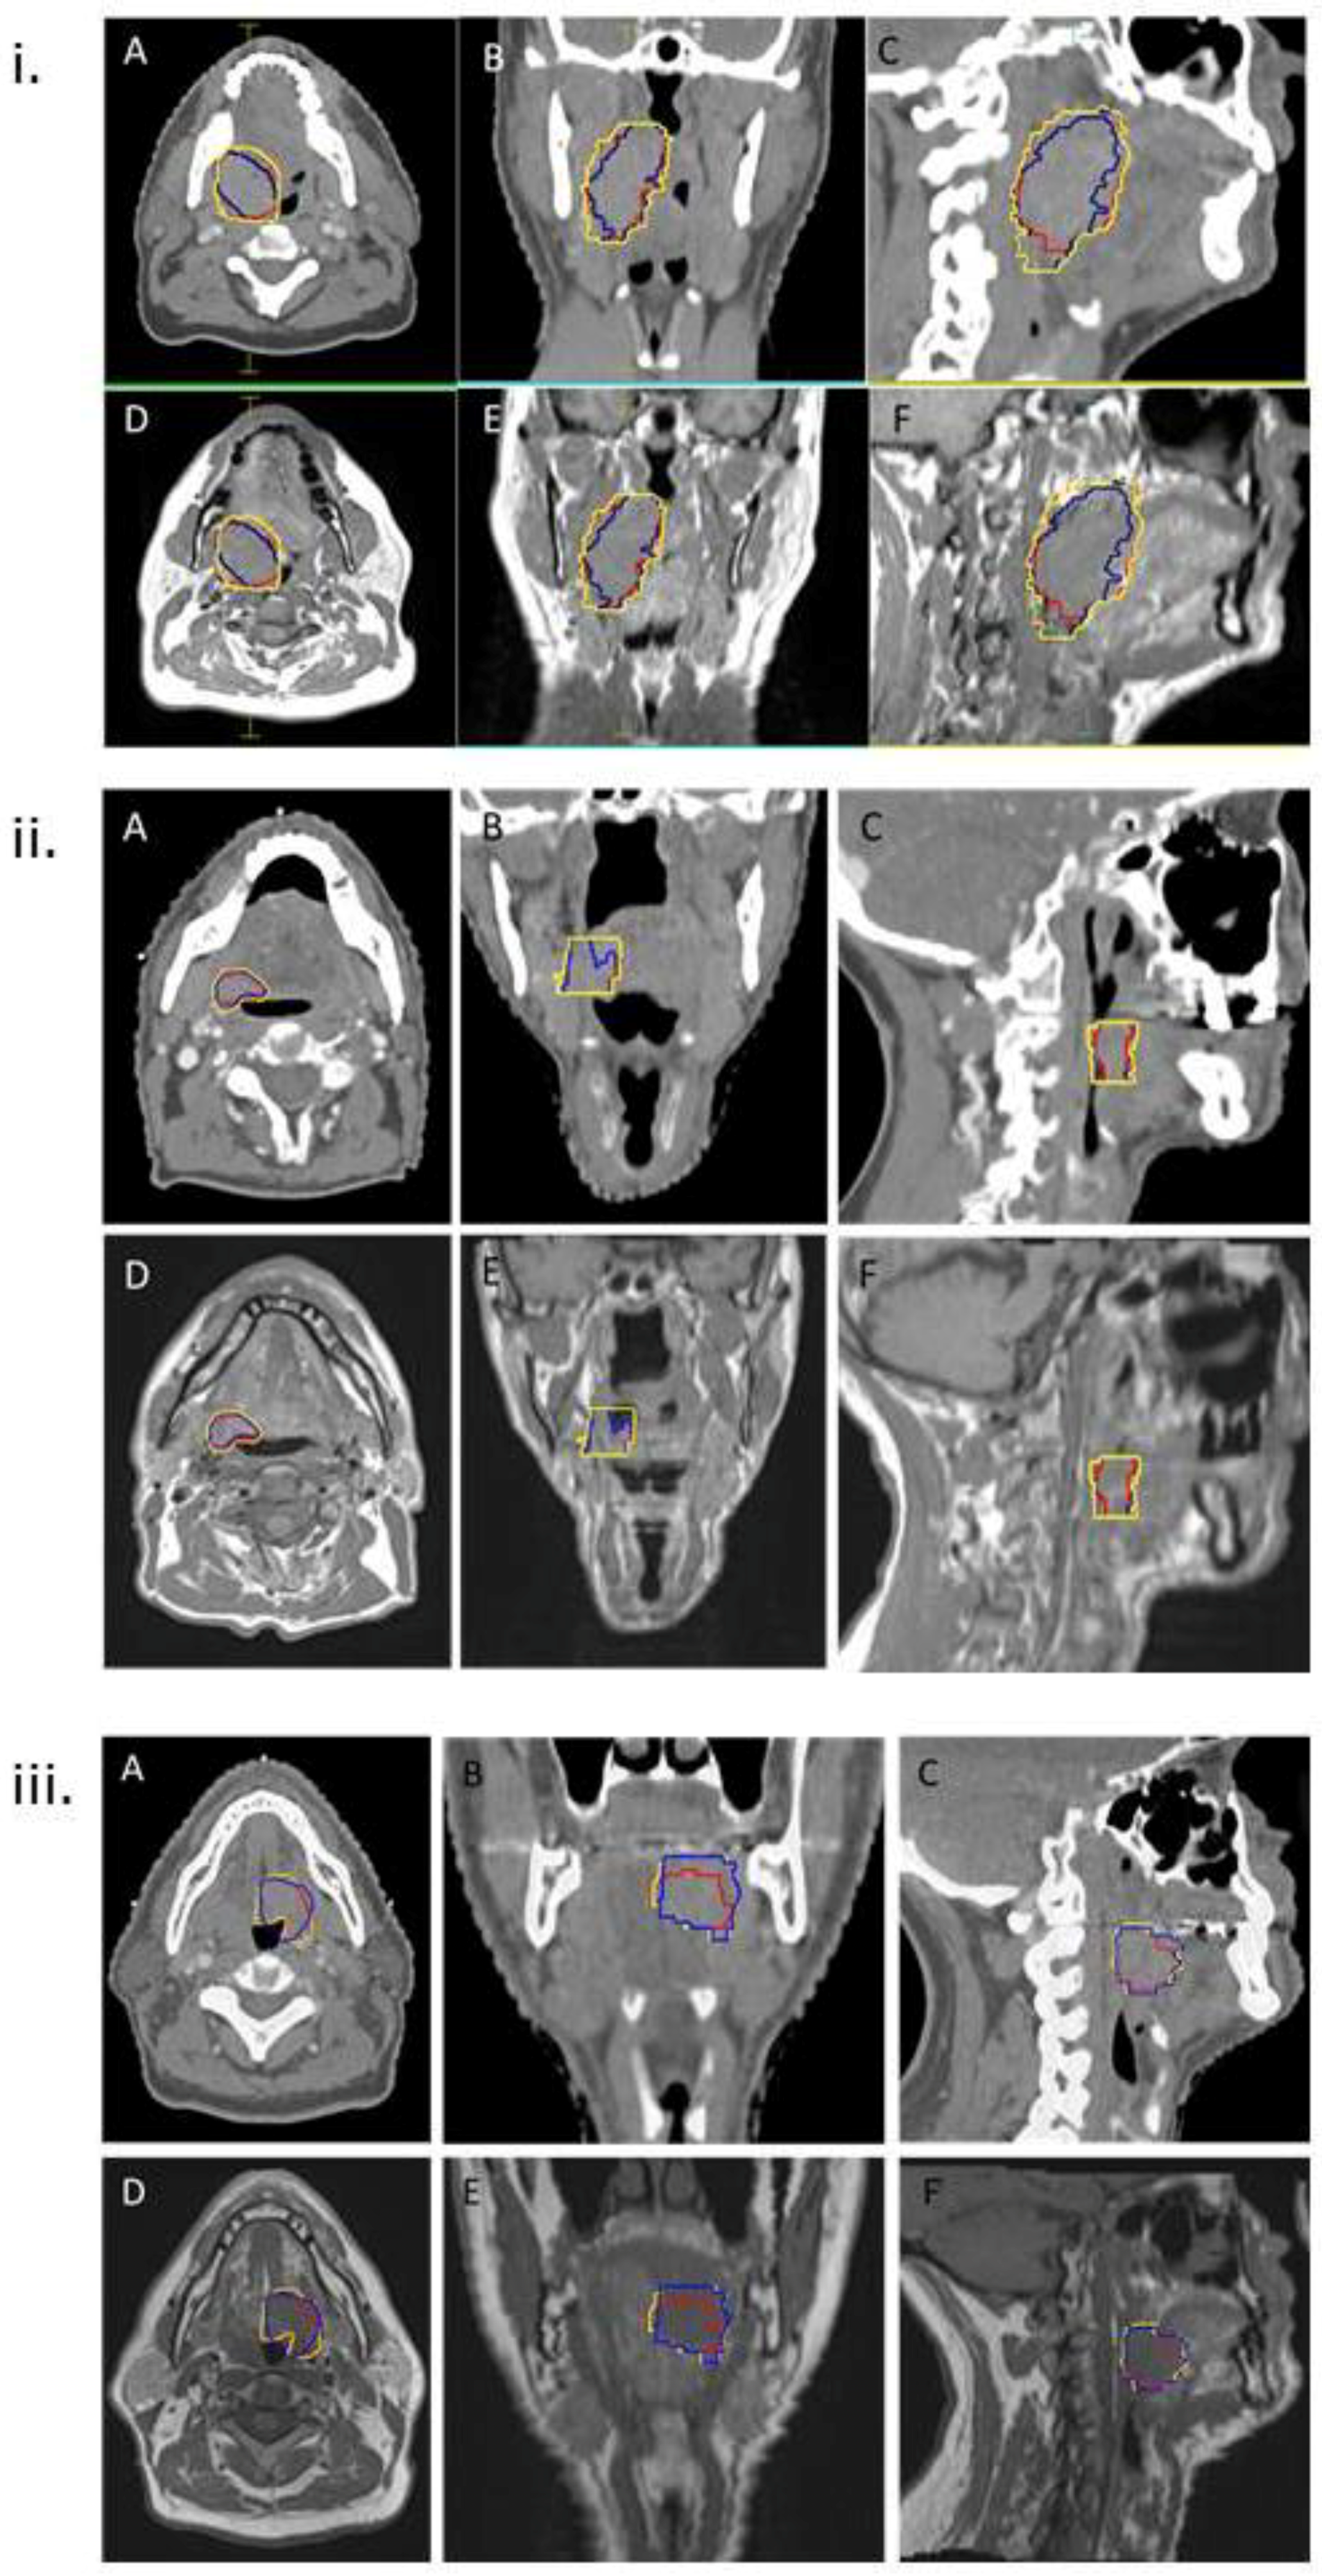

1. Introduction

2.1. Study Population

2.3. Deformable MRI–CT Image Registration

2.4. GTV Delineation

2.5. Analysis of GTVs